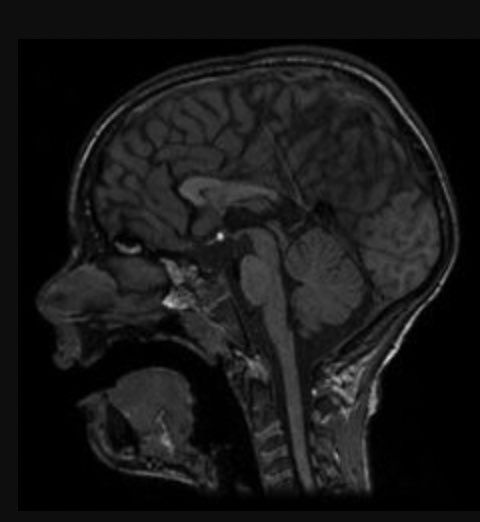

Anomaly detection training to confirm the presence or not of a brain tumor in multi-classifications. 100% accuracy achieved below using 2K images + one training run. Side view 100% certain no tumor detected.✅ Top view 100% certain tumor detected.✅ #AI #Cancer #ML #VCs